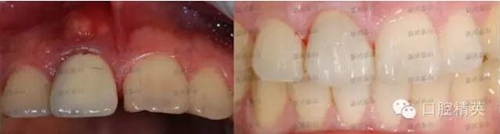

這是一個月前就診的患者,右上中切牙唇側(cè)牙齦有一個大膿包。在照片上可以看到烤瓷牙非常不美觀,一眼就能看出是假的,在前牙的位置,非常明顯,兩牙間還有很大的縫隙,顯得人比較呆板。

去掉烤瓷冠,去掉松動老式螺紋固位釘,其內(nèi)大量的腐爛牙質(zhì),治療之后,剩余牙體很少,如上圖所見。根管治療后,牙齒健康,膿包消失,可以進(jìn)行后續(xù)的治療,讓患者拾回自信。

對比一下前后,視覺沖擊一下吧。

照片角度拍攝有些不一樣,但是變化還是非常明顯的。,右上中切牙唇側(cè)膿包還有點(diǎn)印跡,因個體的差異,慢慢會完全吸收,需要時間。